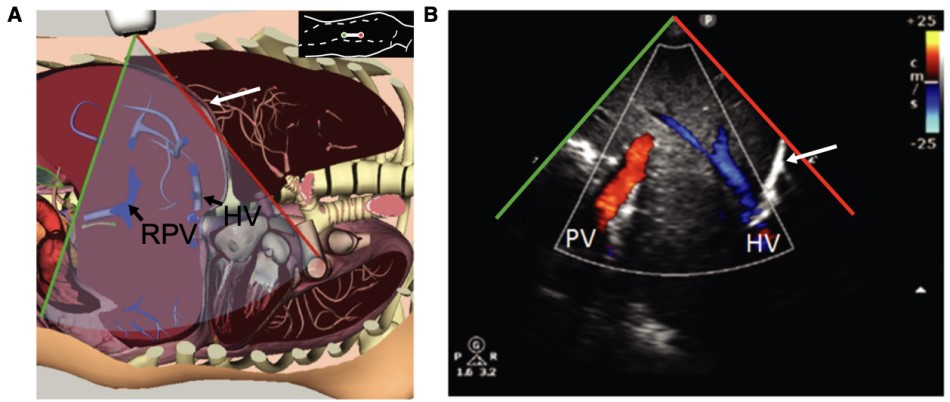

The hepatic vein and portal vein doppler measurements are typically obtained through the liver. The hepatic vein doppler can be obtained from any of the three large hepatic veins that lead into the IVC, whilst the portal vein divides into left and right, either of which can be applicable for this study (Figure 1). The two veins can be differentiated from each other, as the hepatic veins can be traced to the IVC, and the portal vein can be traced to the portal triad. The patient should be supine and the IVC should be first identified. The middle hepatic vein is best approached from a subxiphoid approach while the right hepatic vein is best viewed from a lateral approach. Likewise, the right portal vein is best identified on a lateral view of the liver.

Figure 1. Portal vein and hepatic vein visualization in B-mode6

(Reproduced with permission)

A: Probe placed along right mid to posterior axillary line

B: Color Doppler demonstrates both portal vein (PV) and hepatic vein (HV)